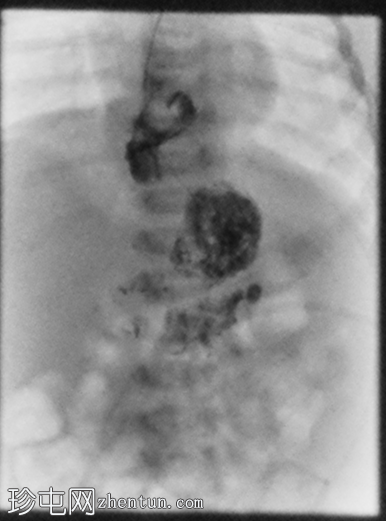

足月新生儿无法耐受任何喂养,经胃管/口服喂养后出现大量呕吐。评估是否存在肠旋转不良和胃排空障碍。

胃部初始显影,并立即反流至食管裂孔疝。在其近端可见管径正常的远端食管。十二指肠降部和横部显影较弱,左上腹可见数段管径较小/部分减压的近端小肠显影。

这是一例儿童患者在透视下发现的食管裂孔疝病例。

最初的临床考虑是肠旋转不良,因为患者频繁且呕吐量大,但后来怀疑这是由中等大小的食管裂孔疝引起的。